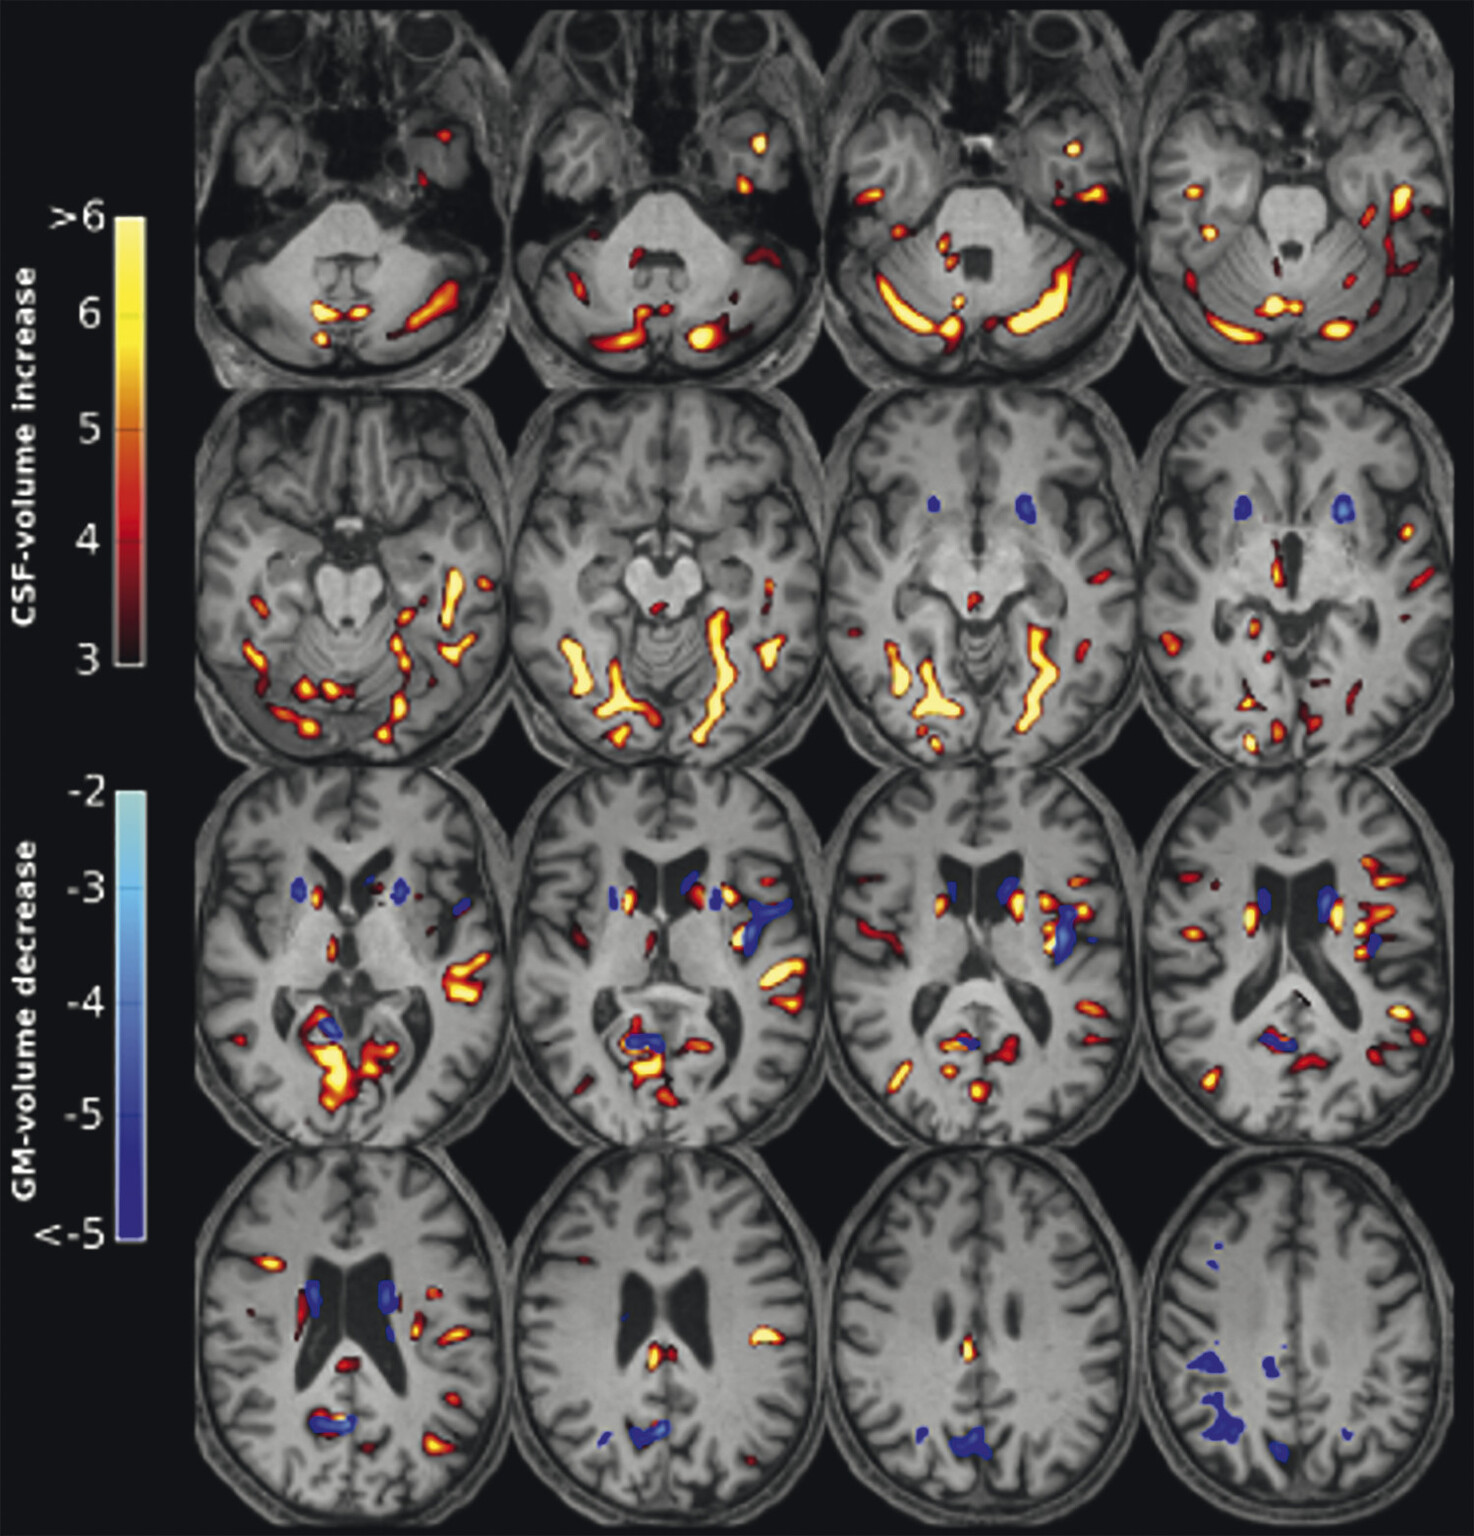

Abb. 69.7 Parkinson-Syndrome: Differenzialdiagnose Multisystematrophie vom zerebellären Prädominanztyp.

67-jährige Patientin mit über Jahre progredienter Verschlechterung des Gleichgewichts, Schluckstörungen und Sprechstörungen. In der T1w 3-D-Sequenz zeigt sich eine ausgeprägte Atrophie des Pons (a, Pfeil), der mittleren Kleinhirnstiele (b, Pfeile) und des Kleinhirns. Diese Veränderungen werden durch die Ganzhirnvolumetrie bestätigt (c): Anomale Regionen der grauen Substanz (mindestens 2 Standardabweichungen unter dem vergleichbaren Volumen des gesunden alters- und geschlechtsgematchten Normkollektivs) sind blau überlagert. Anomale Liquorvolumina (mindestens 2 Standardabweichungen über dem vergleichbaren Volumen des gesunden alters- und geschlechtsgematchten Normkollektivs) sind als rote bis gelbe Überlagerungen auf das individuelle Patientengehirn projiziert. MRT-morphologisch lässt sich somit die Verdachtsdiagnose Multisystematrophie vom zerebellären Prädominanztyp bestätigen.

a Sagittale T1w 3-D-MRT-Sequenz.

b Axiale T1w 3-D-MRT-Sequenz.

c Voxel- und regionenbasierte Analyse.